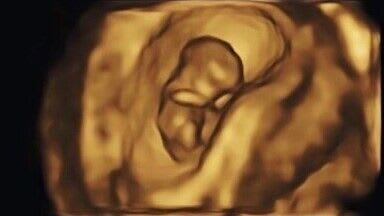

At Numi Scan Basingstoke we realise this is one of the most amazing times in your life. That’s why we provide superior quality images for all of our baby scans.

Our 2D baby scan allows us to check how the baby is doing and provide a wellbeing report with every scan we do. Or alternatively you can go for one of our 4D baby scan packages that includes a wellbeing report, additional 3D photos and even a 4D 'HD Live' movie clips. Letting you share your baby's first smile, Yawn and even get a peek at their tiny little toes with your friends and family!

Once the baby reaches 16 weeks, we can reveal your baby’s gender with our Gender Reveal Scans (99.9% accurate). Either breaking the news with one of our awesome confetti cannons or something a little more discreet. Then from 25 weeks, you can get to see your babies precious face in 3D,4D and HD. Unlike other clinics, HD comes as standard.